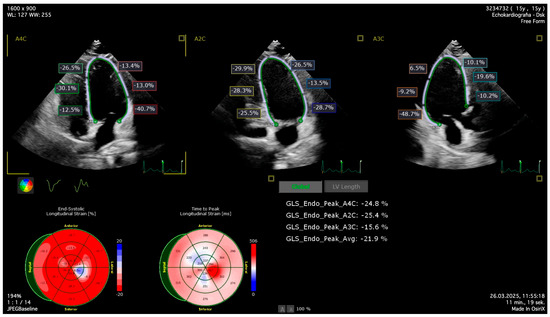

Impact of Acute Lymphoblastic Leukemia Treatment on Left Ventricular Function Assessed in 2D and 3D Speckle Tracing Echocardiography—Preliminary Results

by Julia Haponiuk-Skwarlińska, Halszka Kamińska, Katarzyna Albrecht, Paweł Łaguna and Bożena Werner

J. Clin. Med. 2025, 14(24), 8682; https://doi.org/10.3390/jcm14248682 - 8 Dec 2025

Background/Objectives: Acute lymphoblastic leukemia (ALL) is the most common childhood malignancy with promising survival. ALL treatment involves the use of cardiotoxic anthracyclines. The data for children on new methods of echocardiographic detection of early-onset anthracycline-related left ventricle dysfunction is lacking. Methods: [...] Read more.

Background/Objectives: Acute lymphoblastic leukemia (ALL) is the most common childhood malignancy with promising survival. ALL treatment involves the use of cardiotoxic anthracyclines. The data for children on new methods of echocardiographic detection of early-onset anthracycline-related left ventricle dysfunction is lacking. Methods: Consecutive children with ALL were prospectively enrolled. The echocardiography was performed after ALL diagnosis and before initiation of anthracyclines (first assessment) and after induction and intensification therapy completion (second assessment). The left ventricle echocardiographic assessment involved conventional two-dimensional (2D) echocardiography, 2D speckle tracing, and three-dimensional (3D) echocardiography with offline analysis for 3D speckle tracing. Results: The preliminary group of 32 children presented with mean time between the first and second assessment of 7.3 ± 1.5 months (min.5.3–max.11.4). All children were treated by the same treatment protocol and received doxorubicin and daunorubicin. The mean cumulative equivalent anthracycline dose was 165.6 ± 54.0 mg/m2. Statistically significant differences between the first and the second echocardiography were observed in LV-GLS-2D −24.6 ± 3.3% vs. −21.0 ± 3.3%; p < 0.001, LVEF-3D 59.7 ± 7.3% vs. 55.1 ± 3.0%; p = 0.010, LV-GLS-3D −23.3 ± 5.3% vs. −20.4 ± 2.8%; p = 0.031 and LV-GCS-3D −26.3 ± 5.9% vs. −21.9 ± 3.2%; p = 0.017. The differences in LVEF-2D and LV-GRS-3D were not statistically significant. The decrease of >15% from the first assessment was observed in 9 (28%) in LV-GLS-2D, 8 (25%) in LV-GLS-3D, 11 (34%) in LV-GCS-3D and only in 4 (13%) patients in LV-GRS-3D. Conclusions: Two-dimensional and three-dimensional speckle tracing and 3D-LVEF may be sensitive indicators of subclinical left ventricular function impairment in children treated for ALL with anthracyclines. However, this is a preliminary analysis of the planned cohort; our results should be interpreted with caution. Full article

Show Figures

Figure 1